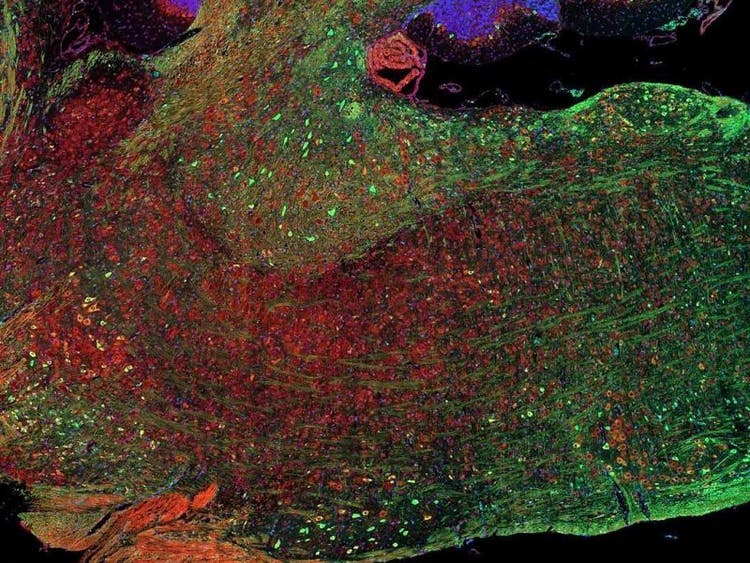

Fluorescence imaging of a mouse brain

While each of these images looks distinct up close, they all come together to form one view of a mouse brain captured with fluorescence imaging.